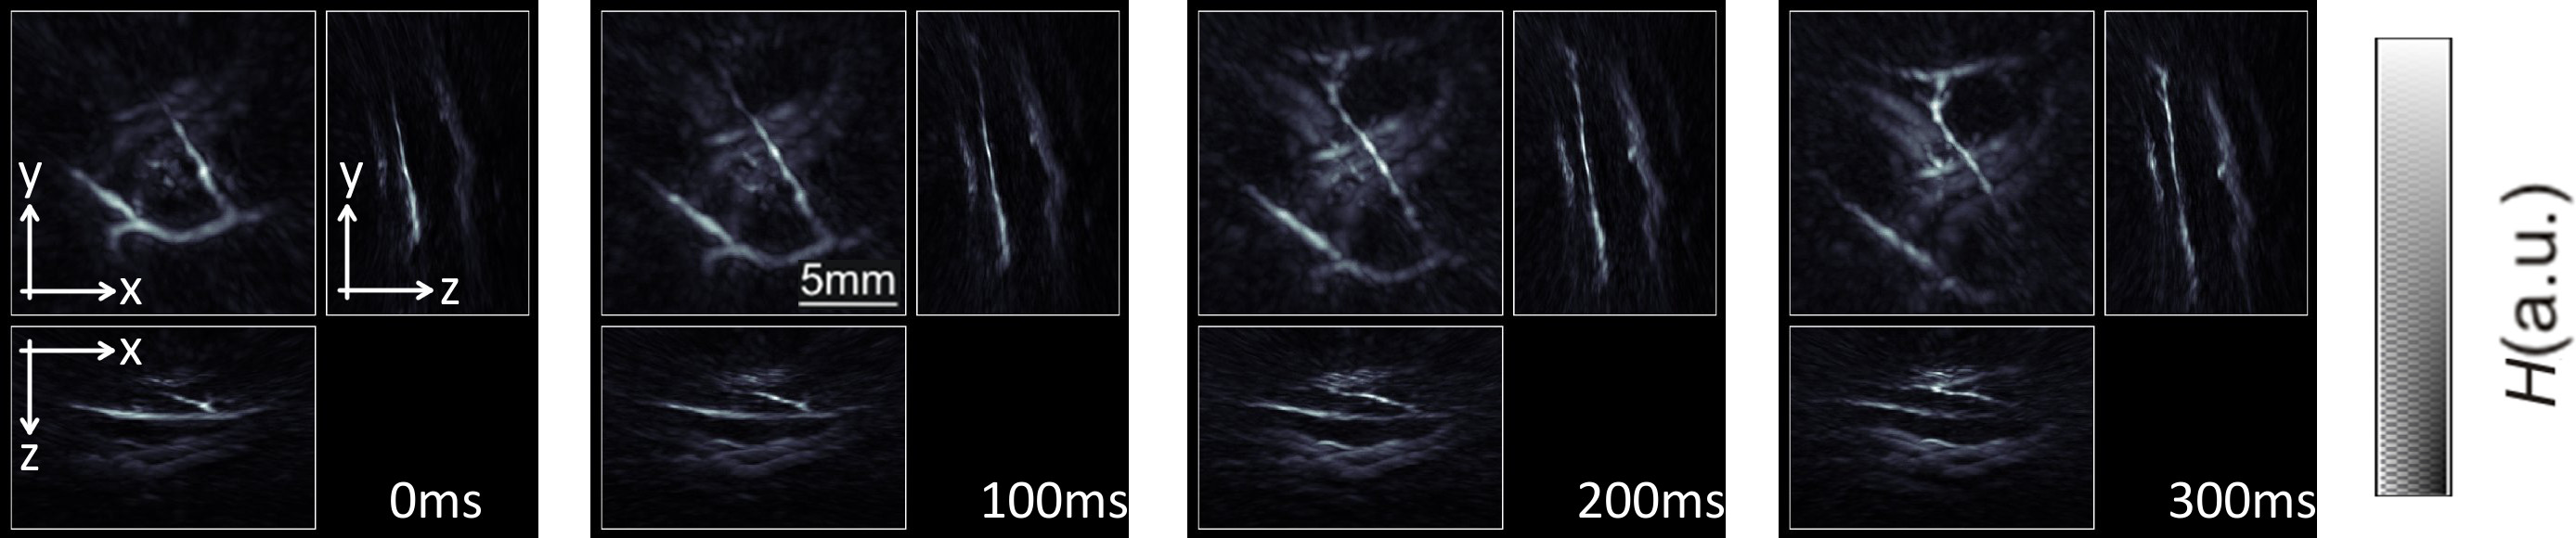

The performance of the probe in real-time tracking peripheral human vasculature is showcased in Figure 2. During the course of this experiment, the probe was slowly scanned along the hand of a healthy human volunteer at a single wavelength of 800 nm with the laser operating at 10 pulses per sec17, so that real-time visualization of the blood vessels for all scanning positions is achieved. The representative maximum intensity projection (MIP) of the reconstructed images in all three directions are displayed in Figure 2. Real-time visualization during the measurement is enabled with a GPU implementation of the filtered back-projection algorithm17.

Figure 2: Tracking of peripheral human vasculature. Maximum intensity projection images of optical absorption along the three Cartesian directions for four consecutive images. Here the laser was operated at 10 pulses per second with a wavelength constantly set at 800 nm. The gray-scale color scheme represents intensity of optical absorption H in the object in arbitrary units. Please click here to view a larger version of this figure.